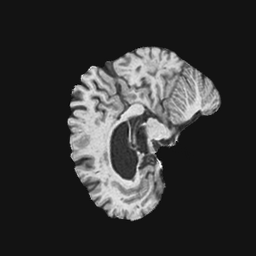

Exp. 1: Segmented adult brain data is used to evaluate our network’s regression performance with known ground truth . 85 brains from the ADNI data set[1] were randomly selected; 70 brains for and 15 brains for . Fig. 2 shows an example slice of the ground truth and the reconstructed .

Reconstructing from initialisation without SVR yields a PSNR of 23.7 1.09; with subsequent SVR the PSNR increases to 29.52.43 when tested on 15 randomly selected test volumes after four iterations of SVR.

Here we show for Exp. 1, Exp. 2, and Exp. 3 randomly selected examples of images that have been presented to the network (ground truth) compared to an image sampled at the predicted location.

In these experiments, we present a ground truth (GT) image to the network to estimate the respective transformation parameters needed to reorient the slice in its correct world co-ordinates. Using the transformation parameters, we generated a slice from the 3D atlas in the location where the network has predicted that slice should be (denoted as SVRNet).

The slices are compared side-by-side to give a visual representation of “where the slice really is” and “where the network thinks the slice is”.

0..5.1 Exp. 1:

Slices, extracted from a correctly registered and reconstructed 3D volume, from the testing data set are presented to the network. The predicted slice is extracted from the same volume, using parameters estimated by SVRNet as shown in Fig. 8 and 9.